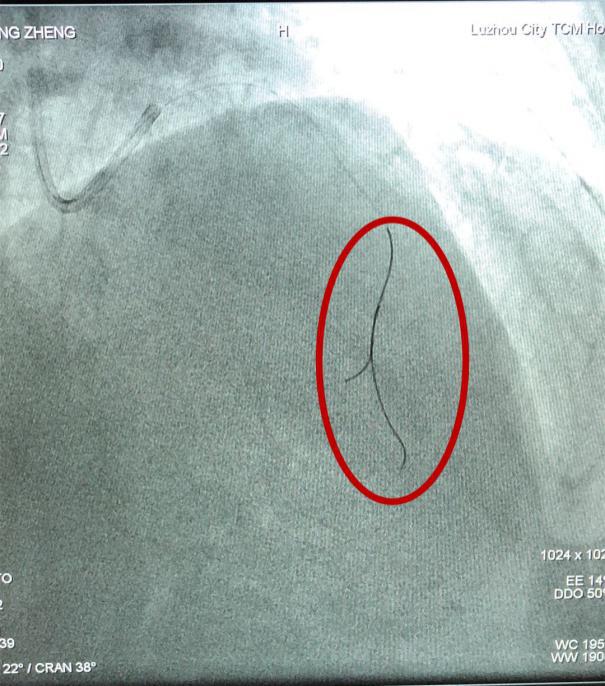

壓力導絲(如圖中紅圈內(nèi)所示)

在冠脈內(nèi)測量FFR(血流儲備分數(shù))